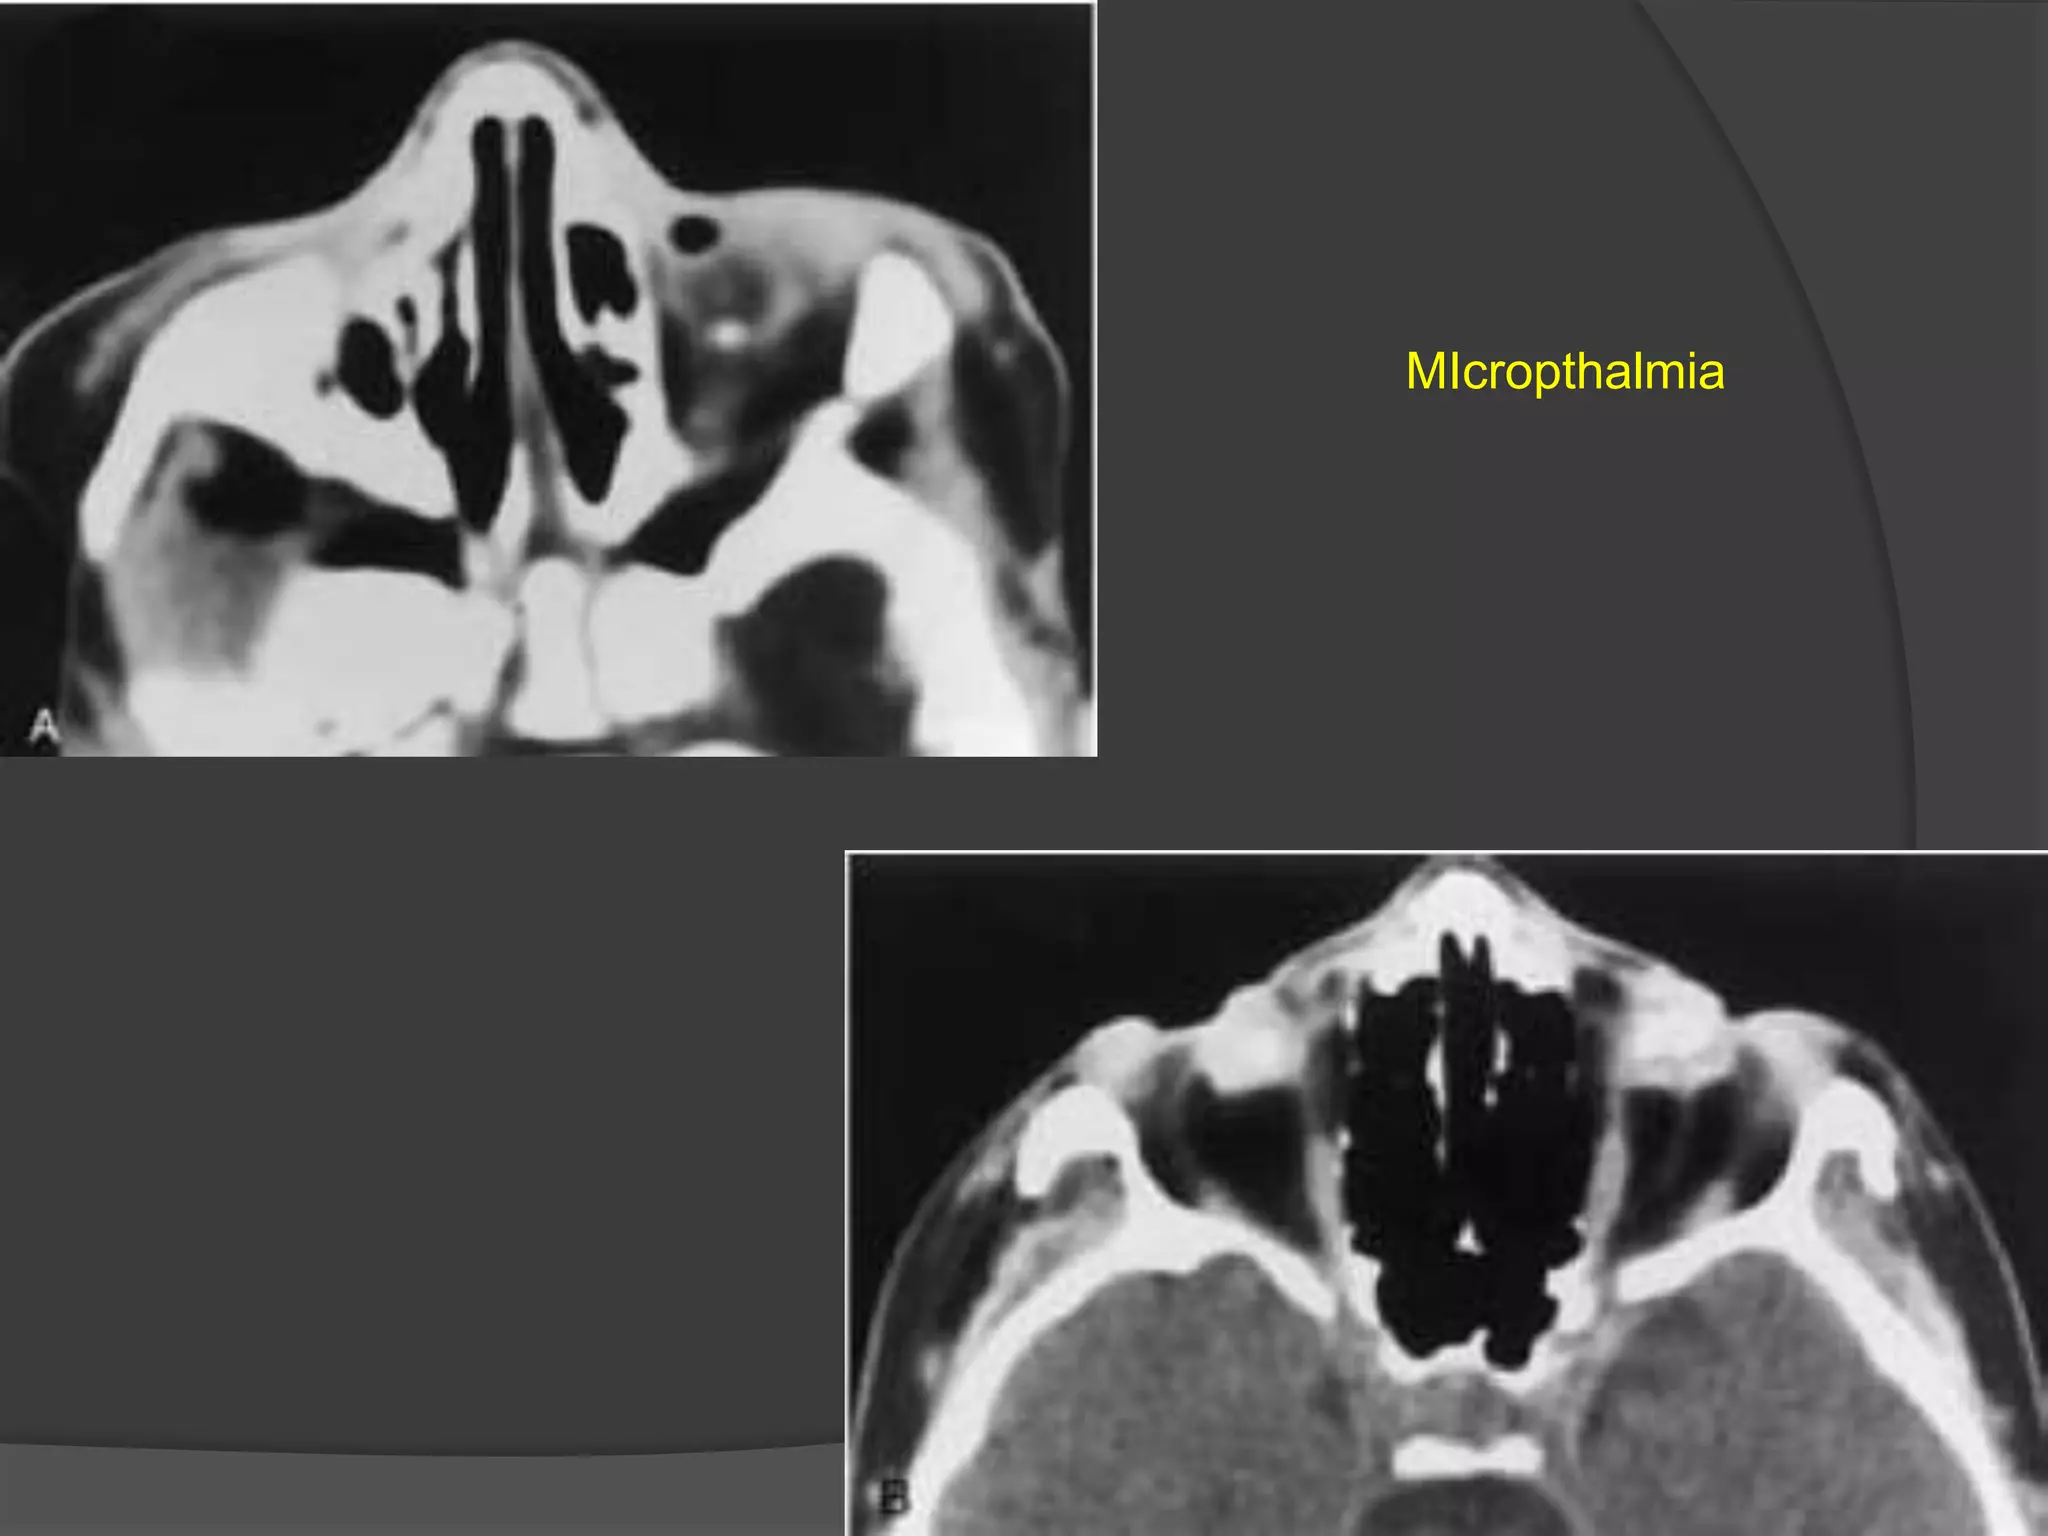

MIcropthalmia

Pthisis Bulbi

• #5 A, Axial CT scan shows a microphthalmic left eye associated with a small calcification. B, Axial CT scan in another patient shows bilateral microphthalmia with marked calcifications.

• #6 Phthisis bulbi: Axial CT scan shows a dense right eye with irregular calcification. This child with acquired immune deficiency syndrome developed cytomegalovirus chorioretinitis, resulting in a disorganized eye with associated dystrophic calcification.